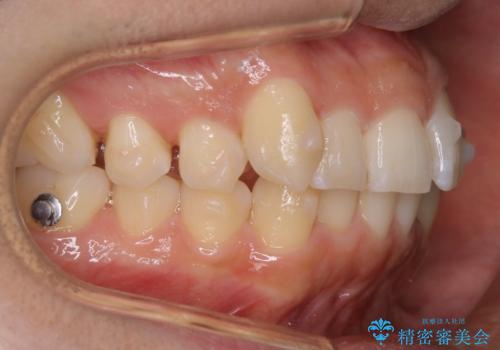

インビザラインで八重歯の治療

- マウスピース(インビザライン)

八重歯と噛み合わせえお治す必要がありましたが、抜歯を必要とするほどの状態ではなかったため非抜歯プランで治療を開始しました。

- 税込 ¥938,000- (インビザライン コンプリヘンシブパッケージ + マイクロインプラント)費用は治療当時の料金となります

マウスピースとマイクロインプラントを組み合わせることで、抜歯をしなくても歯並びを治すためのスペースを作ることができます。奥歯から順に移動させていくので前歯に変化が出るまでには時間がかかりますが、その分健康な歯を抜歯することなく理想的な歯並びを手に入れることができます。